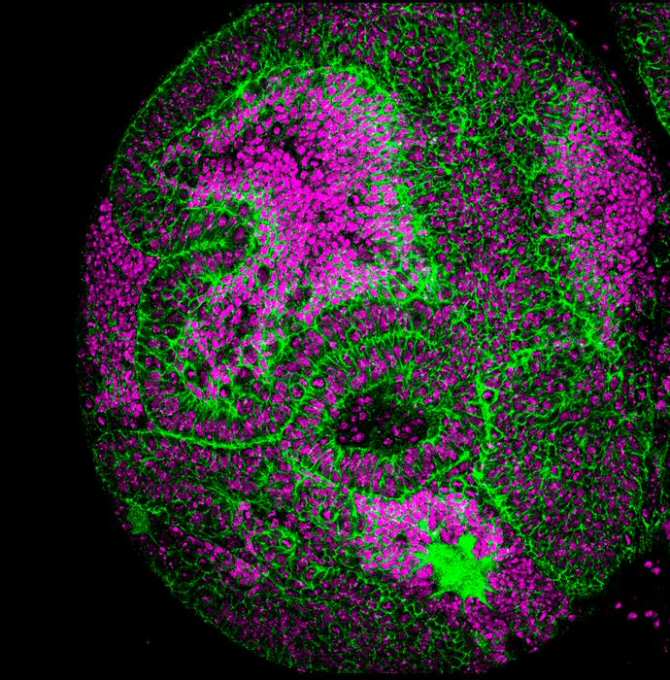

![[Img #72501]](https://noticiasdelaciencia.com/upload/images/05_2024/7325_genes-de-la-linea-germinal-y-desarrollo-de-tumores.jpg)

Dos genes de la línea germinal son esenciales para el desarrollo de tumores cerebrales en las moscas Drosophila. (Imagen: IRB Barcelona. CC BY-NC-ND)